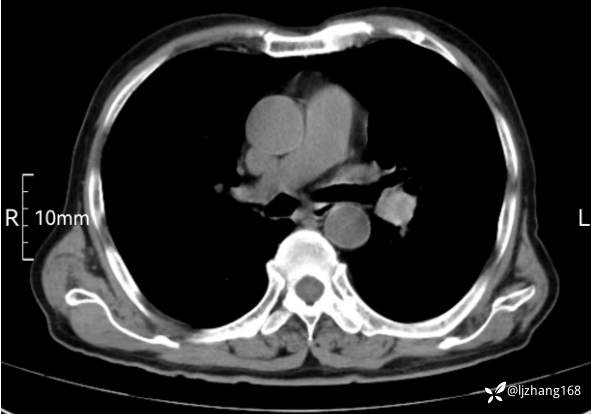

辅助检查:胸部CT:双肺肺气肿,间质性病变,血气分析:PH 7.413, PCO2 29.2mmHg, PO2,81.8mmHg,乳酸 3.3mmol/1,剩余碱-4.0mmol/1,HC03 18.8mmol/1。全血超敏C反应蛋白:超敏C反应蛋白 135.60 mg/L、 白细胞 14x19^9/L,中性粒细胞11.6x10^9/L。